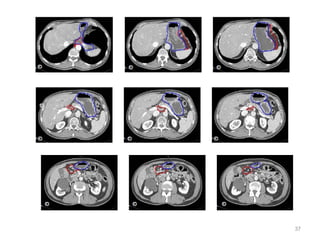

CONTOURING OF TARGET VOLUMES AND

ORGANS AT RISK

24

• Target volume for all gastric cancers would include body of pancreas, full

stomach bed and all regional nodes. Depending on part of stomach

involved, CTV may include also diaphragm, duodenum or lower

esophagus.

• Definition of Target

Volumes

Anastomoses

Gastric bed

Lymph nodes

•Definition of OARs

Kidneys, liver,

lungs, heart, sp

cord

Target and OARs

Which lymph nodes have to be included in the CTV?

• individualize for GE-junction/Cardia (proximal), Corpus (middle)

and antrum (distal) tumors

• GE-junction/Cardia/proximal 1/3: para-oesophageal, perigastric,

hepatogastro lig, perigastric, ,celiac (left gastric artery, celiac

axis), splenic hilum, suprapancreatic, porta hepatis,

pancreaticoduodenal [stations 1-4;7,9-13]

• Corpus/middle 1/3: perigastric, suprapyloric, infrapyloric, celiac

(left gastric artery, common hepatic artery and celiac axis),

splenic hilum, suprapancreatic, porta hepatis,

pancreaticoduodenal [stations 3-13]

• Antrum/distal 1/3: perigastric, suprapyloric, infrapyloric, splenic

artery, pancreaticoduodenal, porta hepatis, celiac (left gastric

artery, common hepatic artery and celiac axis), suprapancreatic

[stations 3-9;11-13] 35